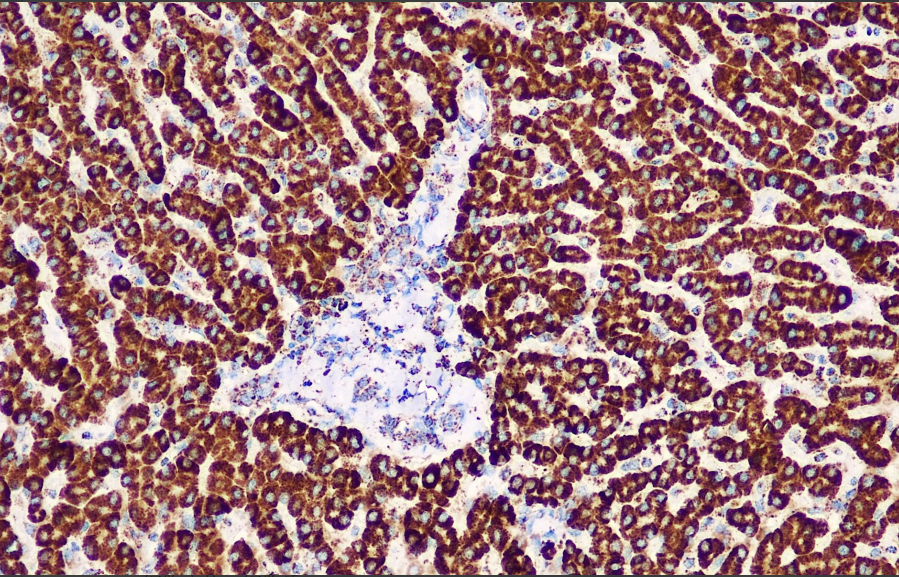

Positive control: Liver

SDHB aids in the identification of SDHB-deficient gastrointestinal stromal tumors, which are often clinically associated with Carney's triad or Carney-Stratakis syndrome. Additionally, SDHB gene mutations are associated with malignant, multicentric, adrenal intra-/extrasurrenal pheochromocytomas, and paragangliomas. This antibody is primarily used in GIST tumor research.

SDHB antibody reagents can specifically bind to SDHB molecular antigens. Immunohistochemistry kits containing SDHB antibody reagents are suitable for the precise diagnosis of succinate dehydrogenase (SDH) deficiency tumors (such as paraganglioma, pheochromocytoma, and gastrointestinal stromal tumor/GIST).